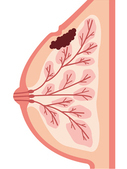

乳がんとは?

乳がんは、乳腺にできるがんです。

日本人女性の9人に1人が乳がんにかかると言われています。

乳がんになる人は30歳代後半から増加し、40歳代以上の年代に多く、この年代の女性のがん死亡原因のトップですが、早期発見・早期治療による10年後の相対生存率は90%以上と言われています。